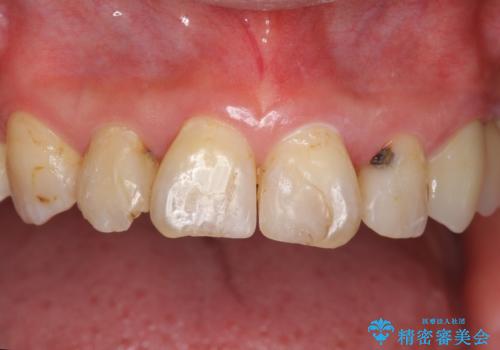

前歯の虫歯 つぎはぎの歯をセラミックに

- 矯正治療後に、前歯の樹脂の詰め物のやりかえを提案していましたが、治療は当時行いませんでした。

その後3年間来院がなく、その間に前歯の虫歯の進行があり、治療を行いました。

やはり、樹脂で虫食い状になってしまうと虫歯が進行しやすくなっているためクラウンがおすすめです。